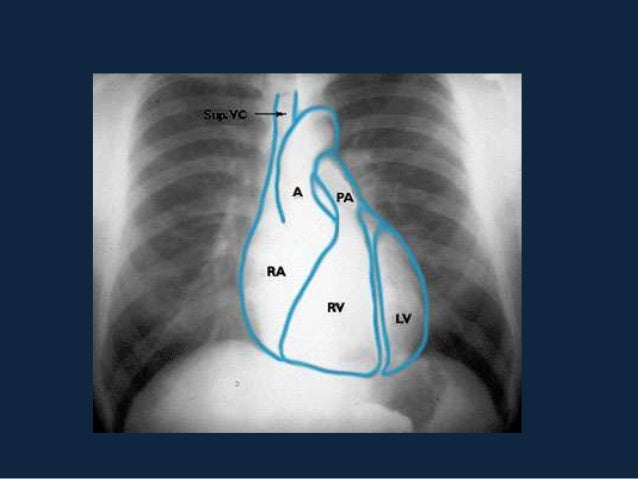

Il trauma del torace è, dopo il trauma cranico, la più frequente lesione nel paziente politraumatizzato, con una incidenza del 4565%, e la più comune causa di morte per trauma (% circa sul totale dei decessi) Pur essendo possibili meccanismi. Nobile Antonio Un gozzo nodulare non operabile ASMaD 11 1 Dott Antonio Nobile Scuola di Formazione in Medicina di Famiglia Regione Lazio. Il mediastino è un compartimento anatomico a forma di clessidra che occupa lo spazio centrale del torace compreso tra i polmoni, in cui sono contenuti il cuore, i grandi vasi ed altre strutture Tutti gli organi e strutture in esso contenuti (cuore, esofago, trachea, grossi vasi e numerosi linfonodi) possono dare luogo a patologie che prendono il nome di "mediastiniche".

INFILTRAZIONE LEUCEMICA LINFADENOPATIA Leucemia acuta, sottotipo a cellule T radiografie del torace di un bambino di 4 anni che mostrano (a) slargamento mediastinico causato da ingrossamento timico;. Il mediastino è un compartimento anatomico a forma di clessidra che occupa lo spazio centrale del torace compreso tra i polmoni, in cui sono contenuti il cuore, i grandi vasi ed altre strutture Tutti gli organi e strutture in esso contenuti (cuore, esofago, trachea, grossi vasi e numerosi linfonodi) possono dare luogo a patologie che prendono il nome di "mediastiniche". Mediastino translation in ItalianEnglish dictionary Showing page 1 Found 97 sentences matching phrase "mediastino"Found in 6 ms.